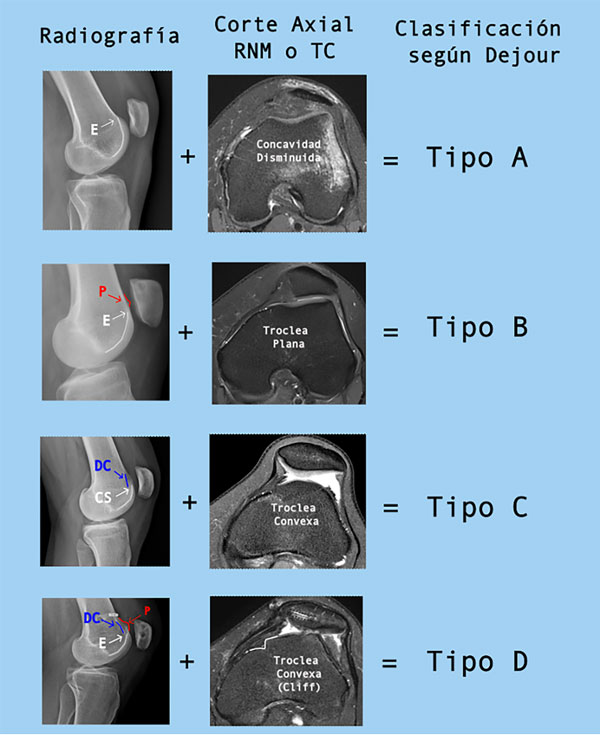

Considerando estos tres signos radiográficos, y el uso de cortes axiales, la displasia troclear puede ser clasificada, según Dejour, en cuatro tipos12 (fig. 1). Esta clasificación ha demostrado tener una adecuada correlación intra e interobservador y es especialmente útil para diferenciar displasias de bajo grado (tipos A y C) y alto grado (tipos B y D).13,14

La combinación de ambas imágenes es mandatoria a la hora de clasificar la displasia troclear ya que ha demostrado aumentar su reproducibilidad cuando se compara con la radiografía como único estudio de imágenes.14,15

Figura 1: Clasificación de D. Dejour para la displasia troclear. E: entrecruzamiento. P: prominencia. DC: doble contorno. (Con autorización de Pineda T, Dejour DH, et al.).15